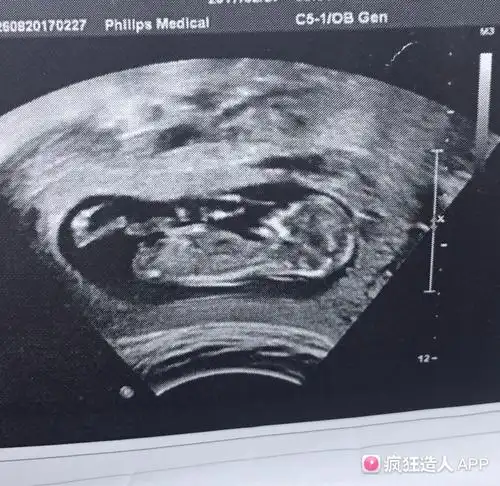

刚做完nt,熟人医生说是男宝,想大家帮忙验证一下

12周3天的nt图看男女,有会看的姐妹帮看看吗

13周nt归来,有没有懂nub理论的姐妹帮看男女呢?